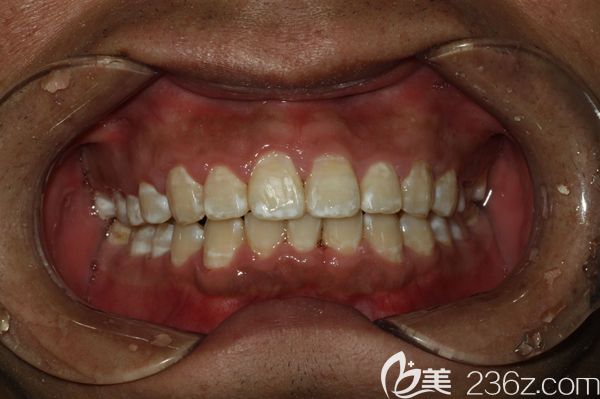

男朋友牙齒太難看,分享和他去廣州陽(yáng)光樹口腔做門牙齙牙深覆蓋矯正后臉型變化圖 b1557 G0 V0

男朋友牙齒太難看了,給大家分享下他在廣州陽(yáng)光樹口腔做門牙齙牙矯正+牙齒排列不齊的深覆蓋臉型變化圖,快來看看他現(xiàn)在變成什么樣了。